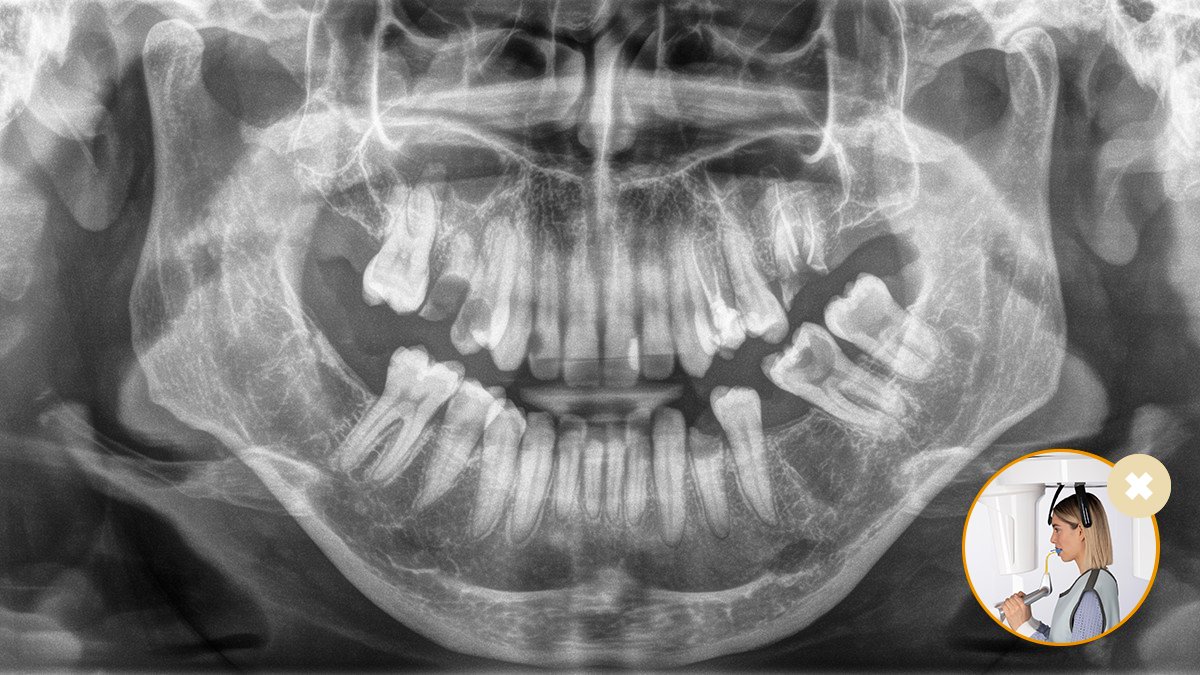

Relaxed and pleasant procedures are equally important for everyone, the patients and the staff alike. It is satisfying and motivating when everything goes according to plan and things go smoothly. The use of Orthophos or Axeos with Sidexis 4 provides you with targeted support. The X-ray systems are simple to use, yet unique in their diagnosis possibilities.. This ensures that every aspect of the treatment process creates a positive experience.

Correct patient positioning leads to high image quality to support an accurate diagnosis and facilitates and improves patient experience.